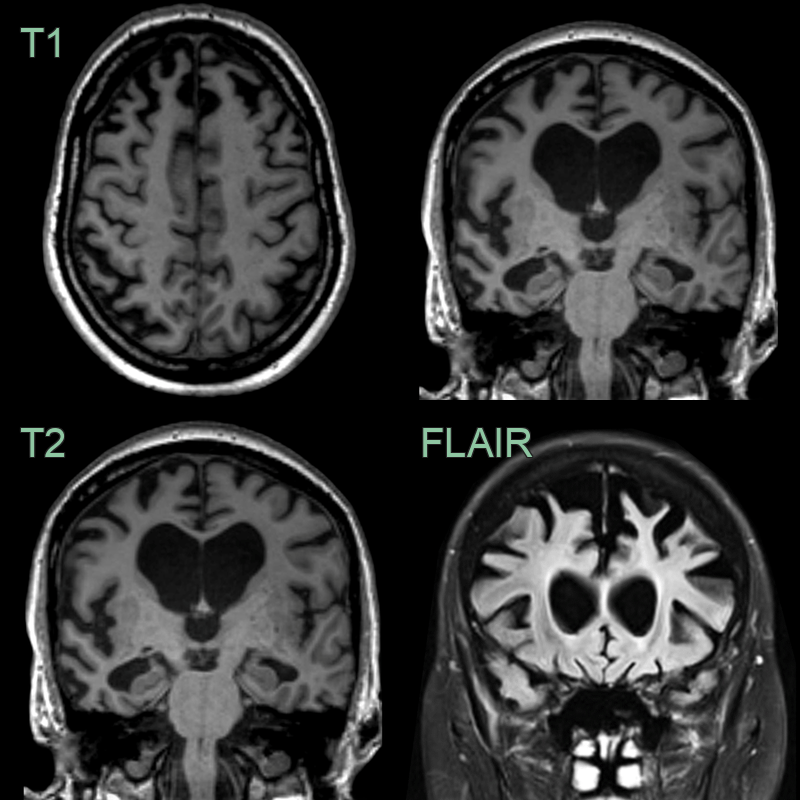

- A 60-year-old patient presented with apathy and increased weight. The patient's partner reported episodes of reckless spending in the preceeding year. The patient had a strong family history for dementia.

- MRI showed symmetrical frontal lobe atrophy. The frontal horns were larger than the trigones. The olfactory sulci were wided ("Crab sign").

- Genetic testing revealed a C9ORF72 mutation as the cause of the frontotemporal dementia.